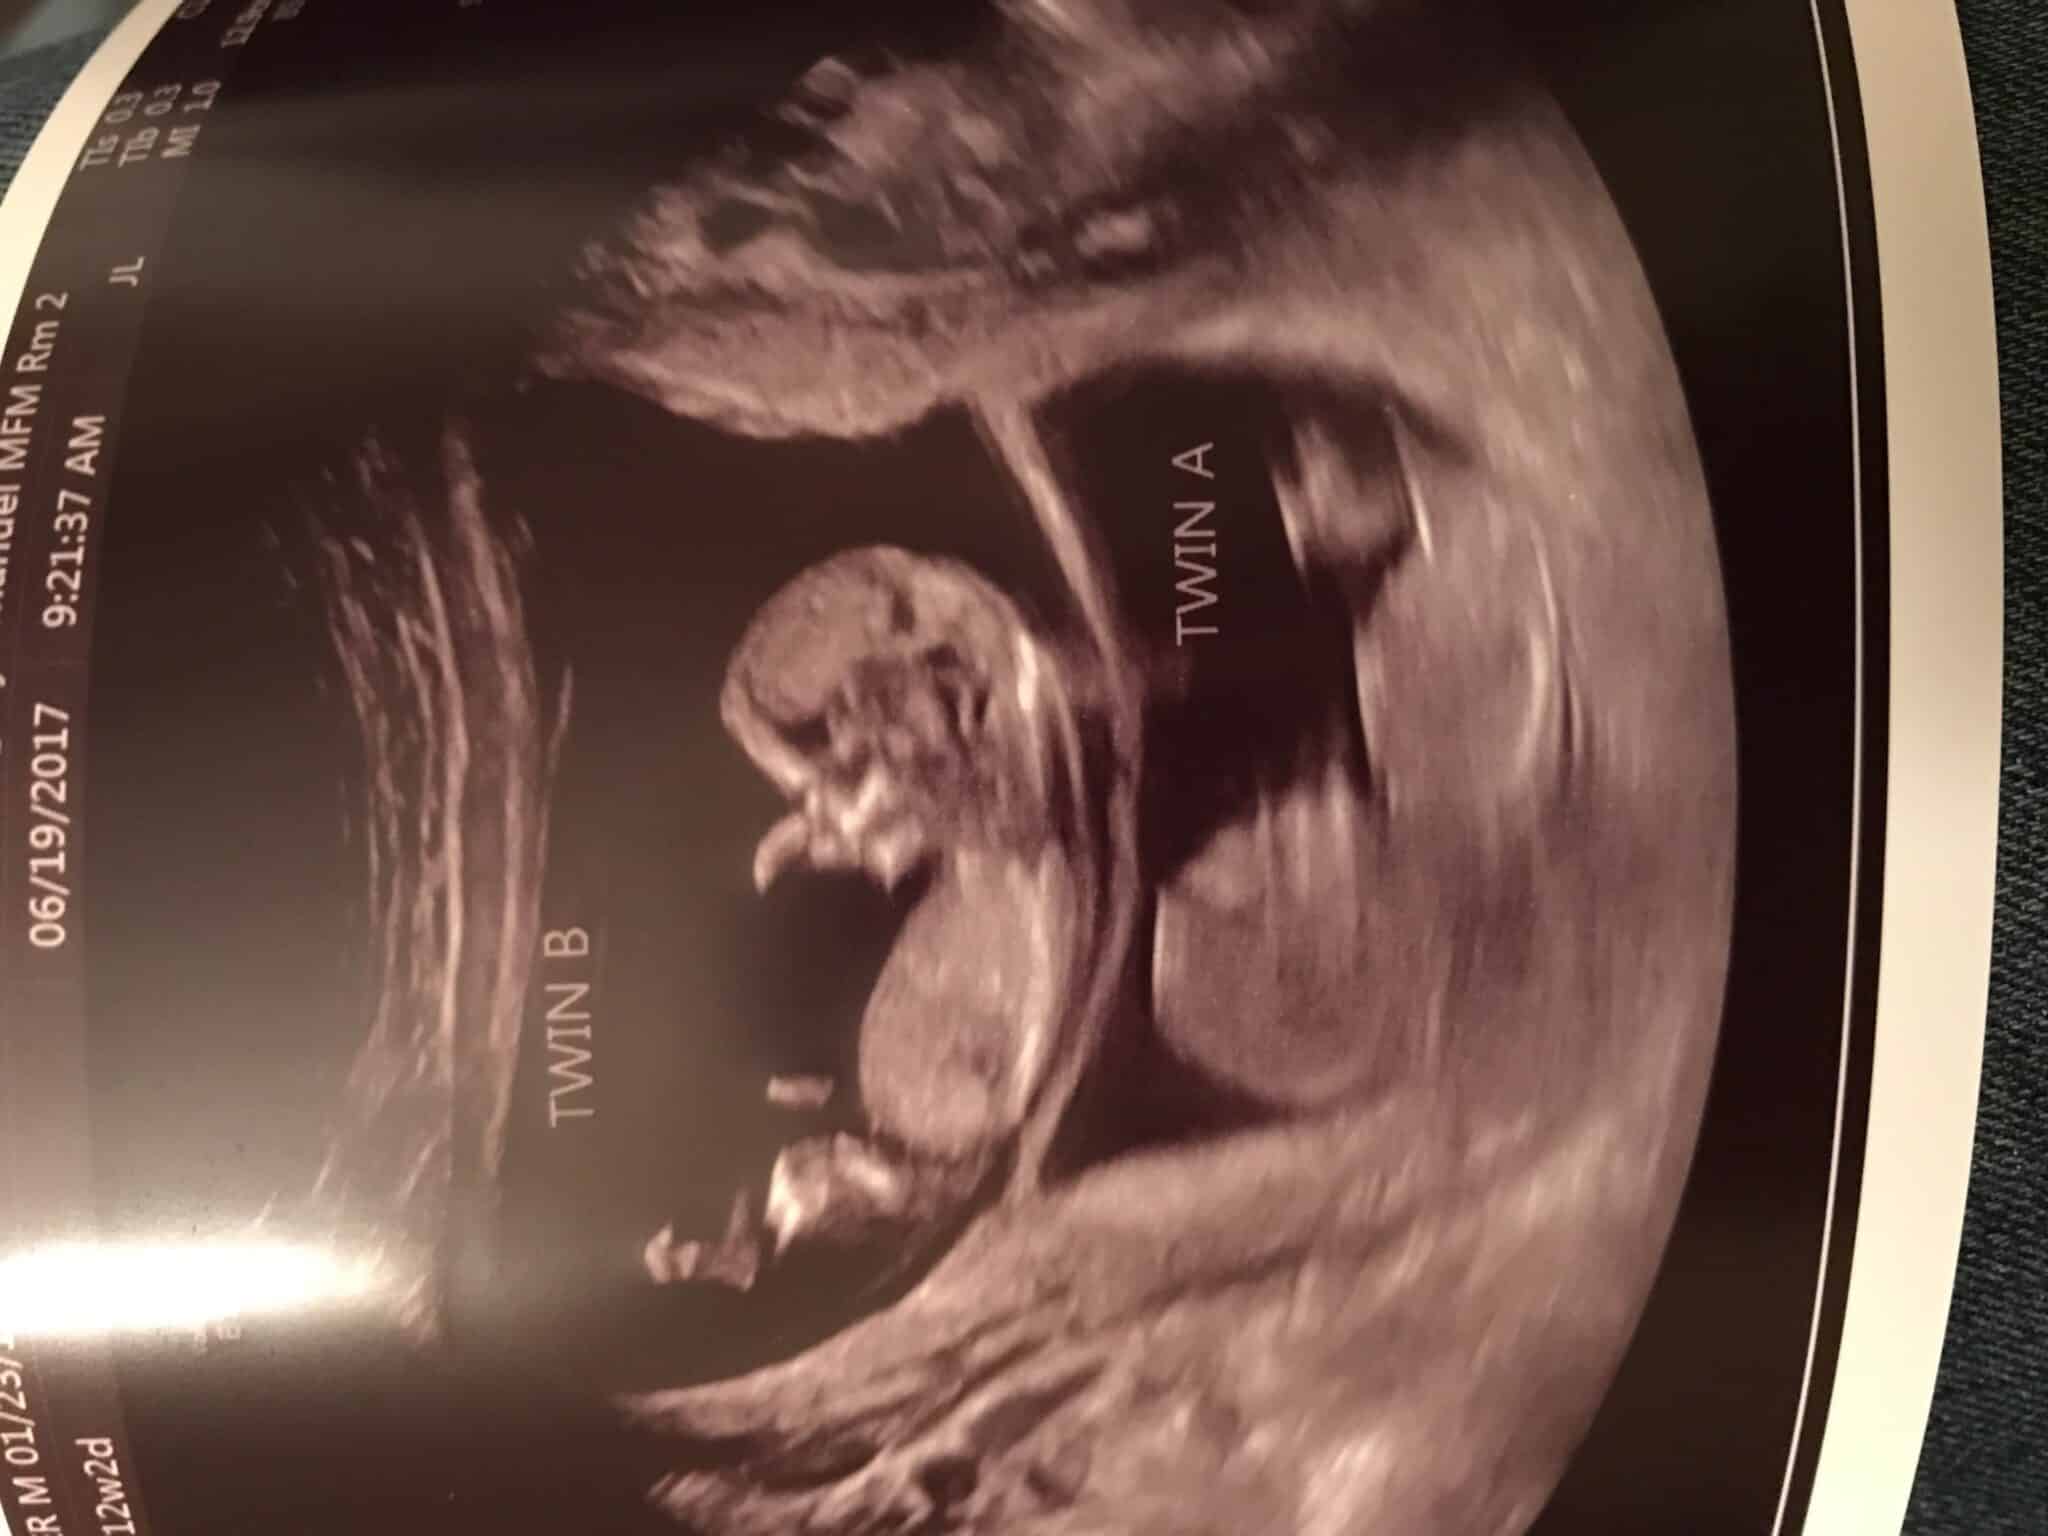

Ultrasound Photos at 12 Weeks Pregnant With Twins